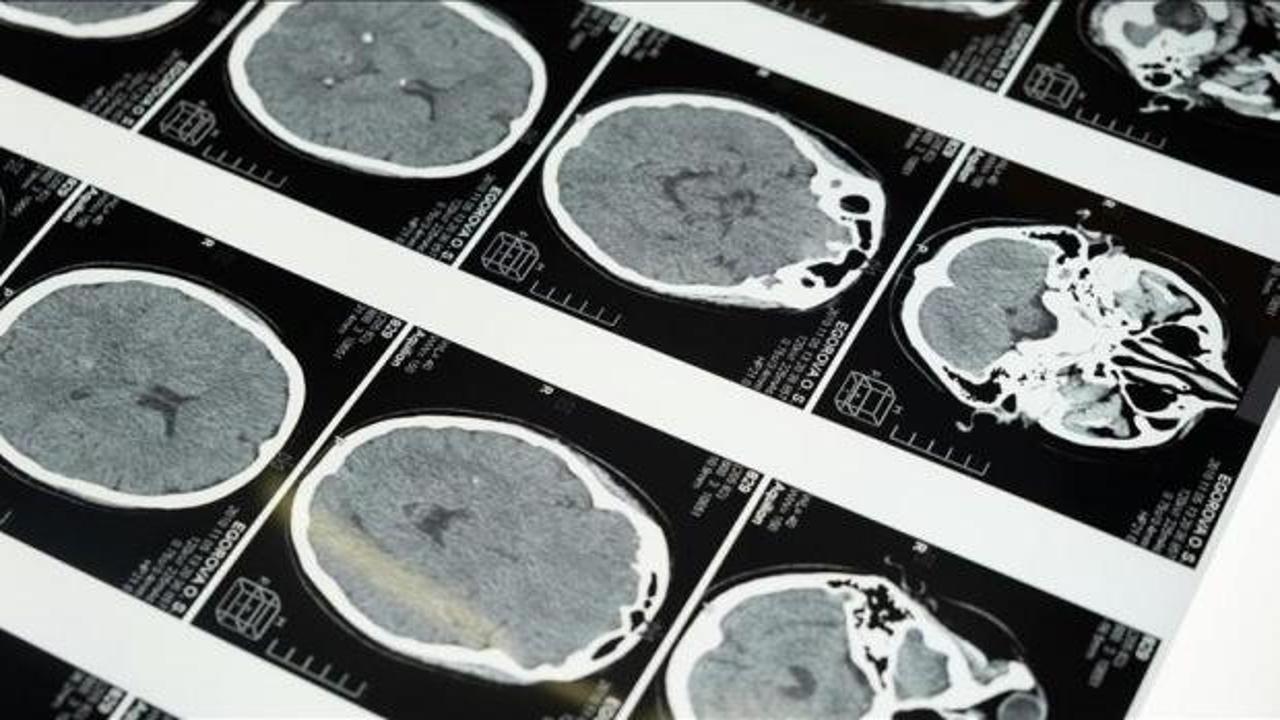

İstanbul'da düzenlenen 1. Dünya Girişimsel Nöroloji ve Nöroşirürji Kongresi'nin (WINNC 2025) düzenleme komitesinde yer alan Eskişehir Osmangazi Üniversitesi Tıp Fakültesi Nöroloji Ana Bilim Dalı Öğretim Üyesi ve İnme Merkezi Sorumlusu Prof. Dr. Atilla Özcan Özdemir, inmenin beyin damarlarının tıkanması (iskemik) ve beyin kanaması şeklinde gelişen iki türünün olduğunu söyledi.

İskemik inmenin dünyada ve Türkiye’de sık görüldüğünü, özellikle kadınlarda görülme sıklığının arttığını ve meme kanserinden daha yaygın hale geldiğini belirten Özdemir, inmenin başlıca ölüm nedenlerinden biri olduğunu ve erişkin yaşta kazanılmış engelliliğin en sık nedeni olması nedeniyle ciddi bir halk sağlığı sorunu haline geldiğini kaydetti.

"Özellikle pıhtıyla tıkanan beyin damarının açılmasıyla ilgili stratejiler gelişti. İnmede erken dönemde yapılan damar açma tedavileri konusunda ülke olarak iyi durumdayız. İnme tedavisinde pıhtıyla tıkalı beyin damarının anjiyo yoluyla açılması mümkün. Böylelikle hastanın 3 ay sonra, 1 yıl sonra kendi işini yapabilecek hale getirilmesi sağlanabiliyor. İnme merkezlerinde uygulanabilen bu işlemi ilk 24 saat içerisinde belirli hasta gruplarına yapabiliyoruz. İlk 24 saat çok kritik, bu müdahaleler de sadece inme merkezlerinde yapılabiliyor."